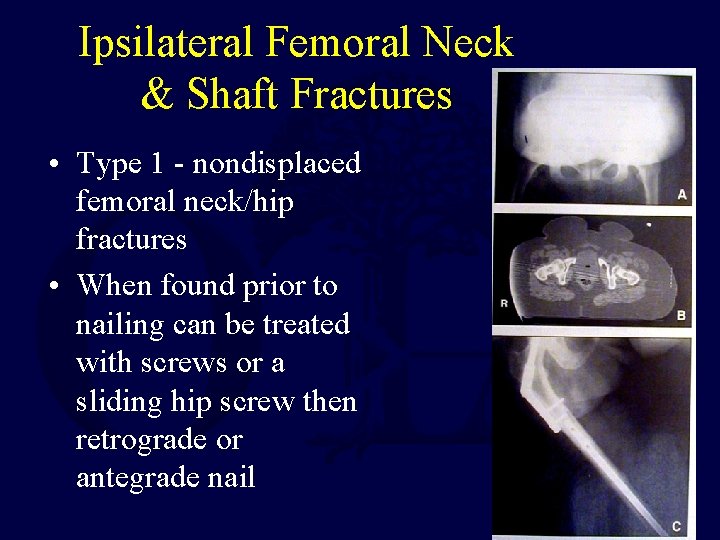

Ipsilateral Femoral Neck & Shaft Fractures • Type 1 - nondisplaced femoral neck/hip fractures • When found prior to nailing can be treated with screws or a sliding hip screw then retrograde or antegrade nail